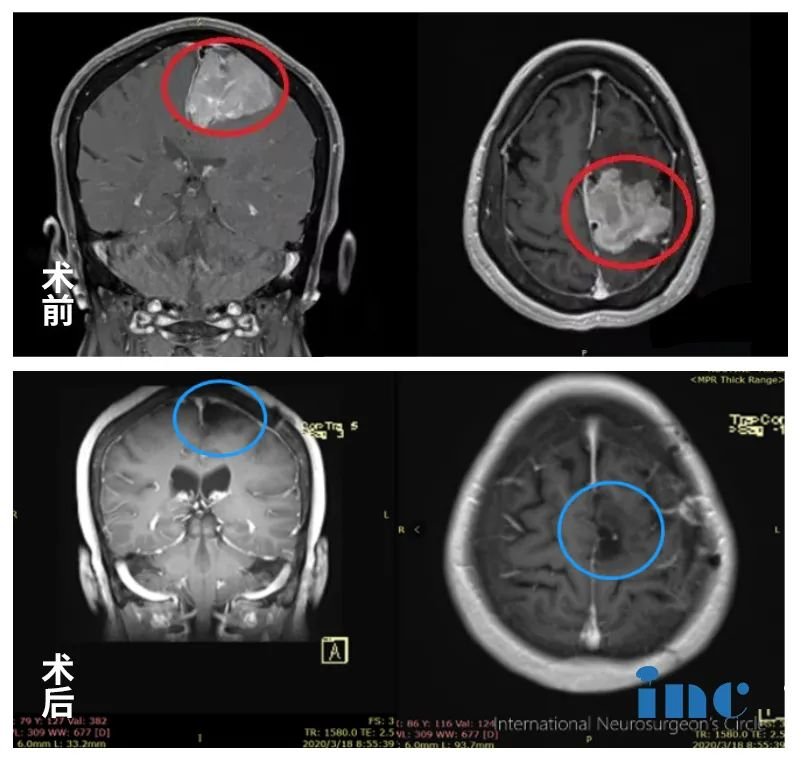

04、矢状窦旁脑膜瘤

简要病史

王阿姨,退休老师,2012年就检查出有“左侧额部大脑镰旁脑膜瘤”,由于肿瘤不到3cm加上无症状,前沿行了保守治疗。2018年复查,脑膜瘤已大于5cm,逐渐出现肢体无力,复查MR显示肿瘤侵犯静脉窦、压迫功能区。国内各大医院求诊,均被告知手术难度大,肿瘤因为靠近大静脉窦难以全切,且肿瘤靠近运动功能区,术后瘫痪可能较大(60-全切不等)。

INC国际教授远程咨询意见

由于王阿姨年事已高,家人努力要帮她寻求有把握的专家来做手术。后通过INC国际神经外科远程咨询德国巴特朗菲教授咨询意见。教授回复——手术可以全切,可以保留矢状窦及相邻静脉,中央前回可以而且需保留,手术风险可以规避,可能不需要术后放化疗。

肿瘤全切、矢状窦成功重建、脑运动功能区无损伤。术后当天即拔插管,术后1天迁出ICU,术后2天可以在护理人员搀扶下走路康复训练,术后5天已经可以独自走路,无需陪同,肢体肌力明显好转,术后1周+,恢复地和正常人一样,精神状态很好。术后1年半,复查MR发现没有肿瘤残余,术前肢体无力明显好转,也无手术后遗症的产生。巴教授建议2-3年再次复查MRI。